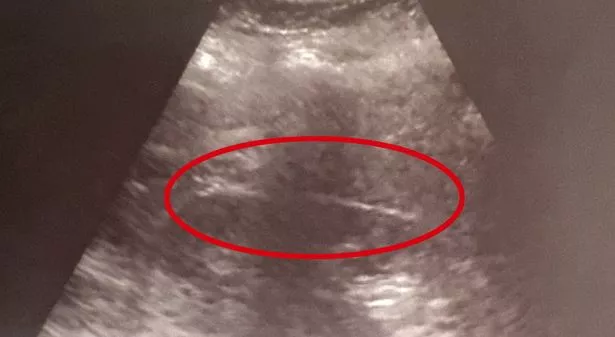

惊慌失措的安布尔试图去拿牙刷,但没有成功,所以她的丈夫开车带她去了克罗地亚卡科韦茨的卡科韦茨县医院,在那里她做了胃部超声波检查。安珀说,医生起初“不相信”她的胃里有一把牙刷,所以她回家过夜,第二天又来做了上腹内窥镜检查。

整个过程花了45分钟才把牙刷从她的胃里取出来(图片:SWNS)